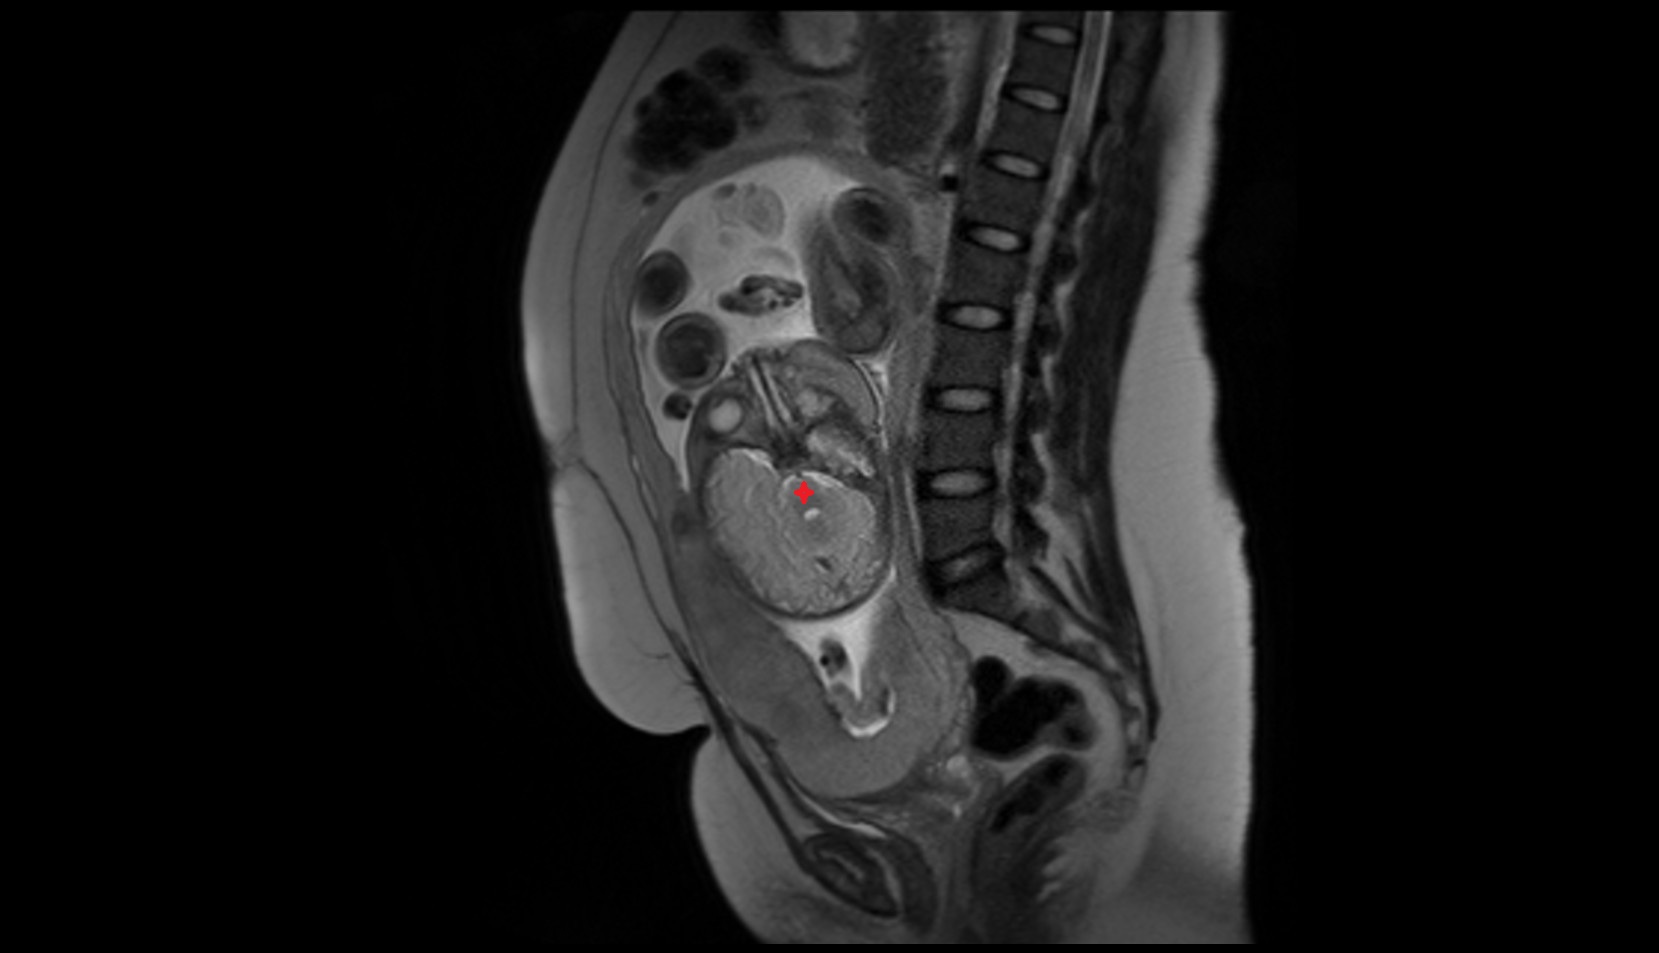

- Placenta

- Uterus (pregnancy)

- Amniotic fluid

- Umbilical cord

- Urinary Bladder in Pregnancy

- Cervix in Pregnancy

- Vagina in Pregnancy

- Fundus of uterus in pregnancy

- Fetal brain